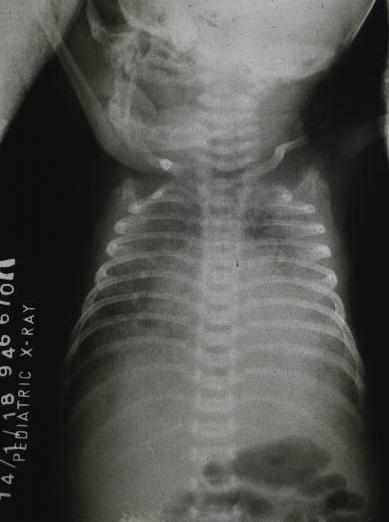

Radiography of the male infant with pulmonary TB : Chest x-ray of the same infant of the above infected with mycobacterium tuberculosis.